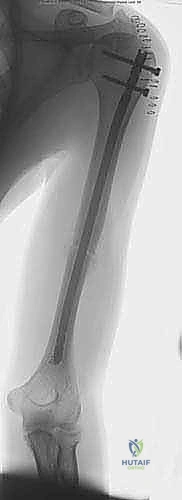

كسر عظم العضد هو إصابة شائعة، وعلاجه بالمسمار النخاعي الأمامي هو إجراء جراحي فعال لتثبيت الكسر داخليًا، مما يساهم في الشفاء السريع واستعادة وظيفة الذراع. يتميز بكونه طفيف التوغل ويحافظ على إمداد الدم، ويقدم الأستاذ الدكتور محمد هطيف هذه الجراحة بخبرة عالية.

الخلاصة الطبية السريعة: يُعد كسر عظم العضد (Humerus Fracture) من الإصابات الشائعة والمعقدة في جراحة العظام، ويتطلب تدخلاً دقيقاً لضمان عودة الوظيفة الكاملة للذراع. يُعتبر العلاج باستخدام "المسمار النخاعي الأمامي" (Antegrade Intramedullary Nailing) ثورة في عالم جراحة العظام، حيث يوفر تثبيتاً داخلياً قوياً بتقنية طفيفة التوغل تحافظ على التروية الدموية الحيوية للعظم، مما يسرع من عملية الالتئام. يقدم الأستاذ الدكتور محمد هطيف، أستاذ جراحة العظام والمفاصل بجامعة صنعاء، هذا الإجراء الجراحي المتقدم بخبرة تتجاوز العشرين عاماً، مستخدماً أحدث التقنيات لضمان أعلى نسب النجاح وأقل نسب المضاعفات لمرضاه في اليمن.

التثبيت بالمسمار النخاعي الأمامي: المعيار الذهبي الحديث

يُعد "المسمار النخاعي الأمامي" (Antegrade Nailing) - أي الذي يتم إدخاله من جهة الكتف نزولاً نحو الكوع - قمة التطور في علاج كسور منتصف وأعلى عظم العضد. تعتمد هذه التقنية على مبدأ "التثبيت البيولوجي" (Biological Osteosynthesis). بدلاً من فتح الذراع بالكامل لترتيب قطع العظم بدقة هندسية (مما يقتل التروية الدموية)، يتم إدخال سيخ معدني قوي (مصنوع من التيتانيوم المتوافق حيوياً) داخل تجويف العظم ليعمل كدعامة داخلية، مع ترك الكسر المفتت في بيئته الدموية الطبيعية الغنية بالخلايا الجذعية لتلتئم بسرعة.